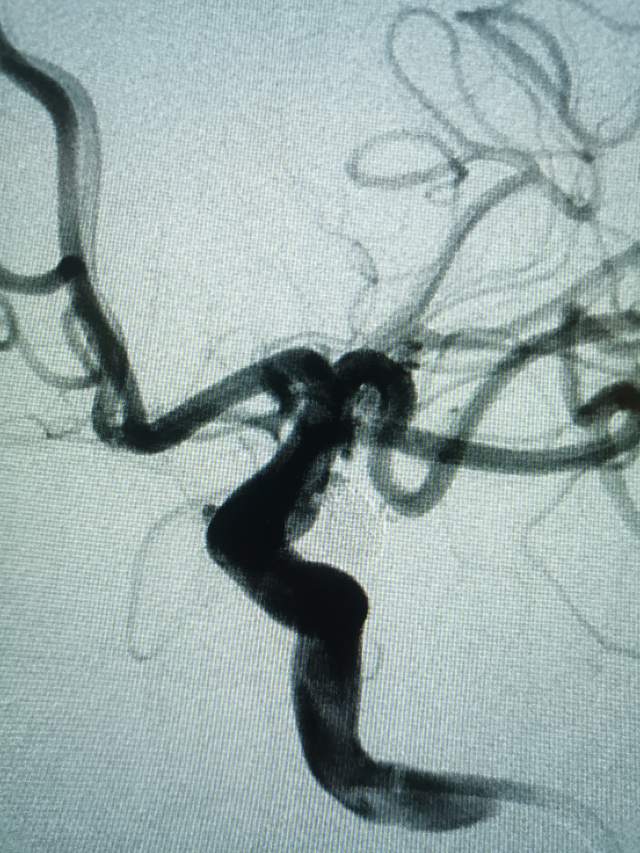

午夜,54岁中年女性,颅内多发动脉瘤破裂出血 ,一个左侧A1动脉瘤,一个左侧胚胎型大脑后动脉瘤(责任动脉瘤;起始部和远端上壁各见一个小泡,后面这个为破裂点;起始部累及粗大胚胎型大脑后动脉),

急诊绿色通道给予责任动脉瘤栓塞,远端破裂小泡完全不显影,近端瘤颈处小泡也基本不显影,胚胎性大脑后动脉保留良好。